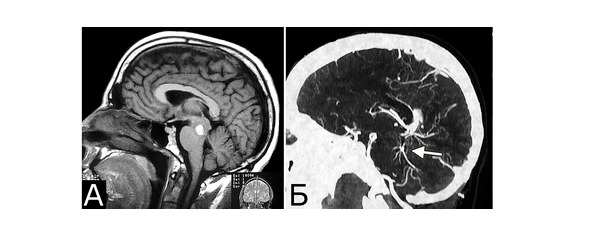

У 6 больных каверномы сочетались с венозными ангиомами и аномалиями венозной системы. Крупные патологические вены, расположенные в непосредственной близости к КМ, часто обнаруживают при МРТ или на операции, в связи с чем многие авторы рассматривают их как единую патологию (28, 93, 154, 351, 357). Тем не менее, в ряде случаев кавернозные и венозные мальформации можно четко дифференцировать как самостоятельные образования, особенно если они находятся в разных отделах мозга. У двух больных патология венозной системы представляла собой аномалию сразу нескольких крупных венозных коллекторов головного мозга (рис. 2).

Рис. 2. Б-ной П, 22 г. Сочетанная сосудистая патология мозга: Множественные КМ головного мозга. Аномалия развития венозной системы мозга. А – КМ височной, теменной и затылочной долей слева (МРТ, режим Т2, аксиальная проекция). Б, В – аномалия развития костей и оболочек мозга в виде локальной деформации внутренней костной пластинки и губчатого вещества теменных костей в области впадения патологической вены в ВСС. Расщепление аномального ВСС на две лакуны, пролабирование мозга в область дефекта (МРТ, режим Т1, сагиттальная и фронтальная проекции). Г – аномалия венозной системы в виде отсутствия прямого синуса, формирования крупной патологической вены, впадающей в заднюю треть ВСС (МРТ-АГ, сагиттальная проекция)